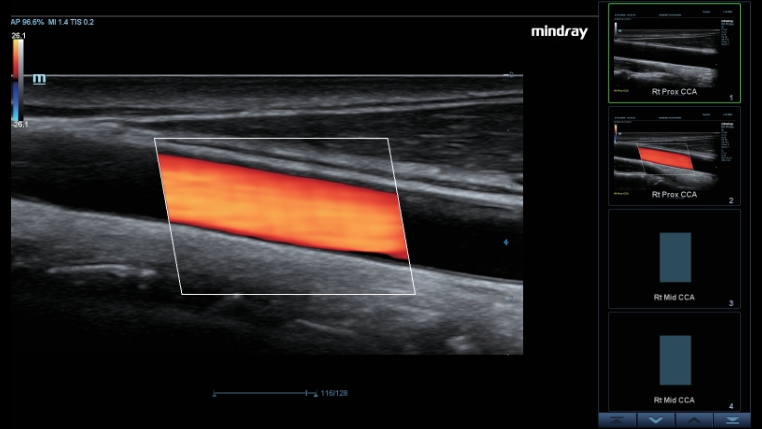

Smart Track

Smart Track bietet eine schnelle und intelligente Optimierung f├╝r die vaskul?re Bildgebung mit einer einfachen One-Touch-Aktion. Es kann Farbe, Leistung und das PW-Spektrum optimieren durch Self-Tracking und zeitintensivere Schritt reduzieren. Deshalb ist der Workflow der vaskul?ren Untersuchen mit einer optimalen Ansicht vereinfacht.